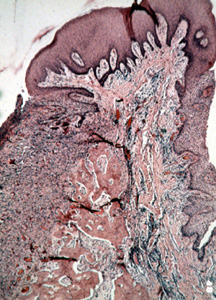

Esta microfotografía de baja resolución muestra  varios componentes del tejido. Hay áreas de tejido conjuntivo celular y zonas de inflamación crónica. Además, usted puede ver las numerosas trabéculas óseas que a  menudo están presentes.

A una mayor resolución de imagen  se observan  áreas hipercromáticas como de la condensación de fibroblastos. Hay condensación ligera de colágeno que indica la posible formación de hueso. Es una lesión hiperplásica.

Ilustrado aquí es el área central de tejido conjuntivo celular con el epitelio encima y trabéculas de hueso al fondo. La presencia de hueso es común.

A menudo se  presentan cuerpos calcificados pequeños. (cementículos)

Casi cualquier tipo de calcificación puede encontrarse en estas lesiones.